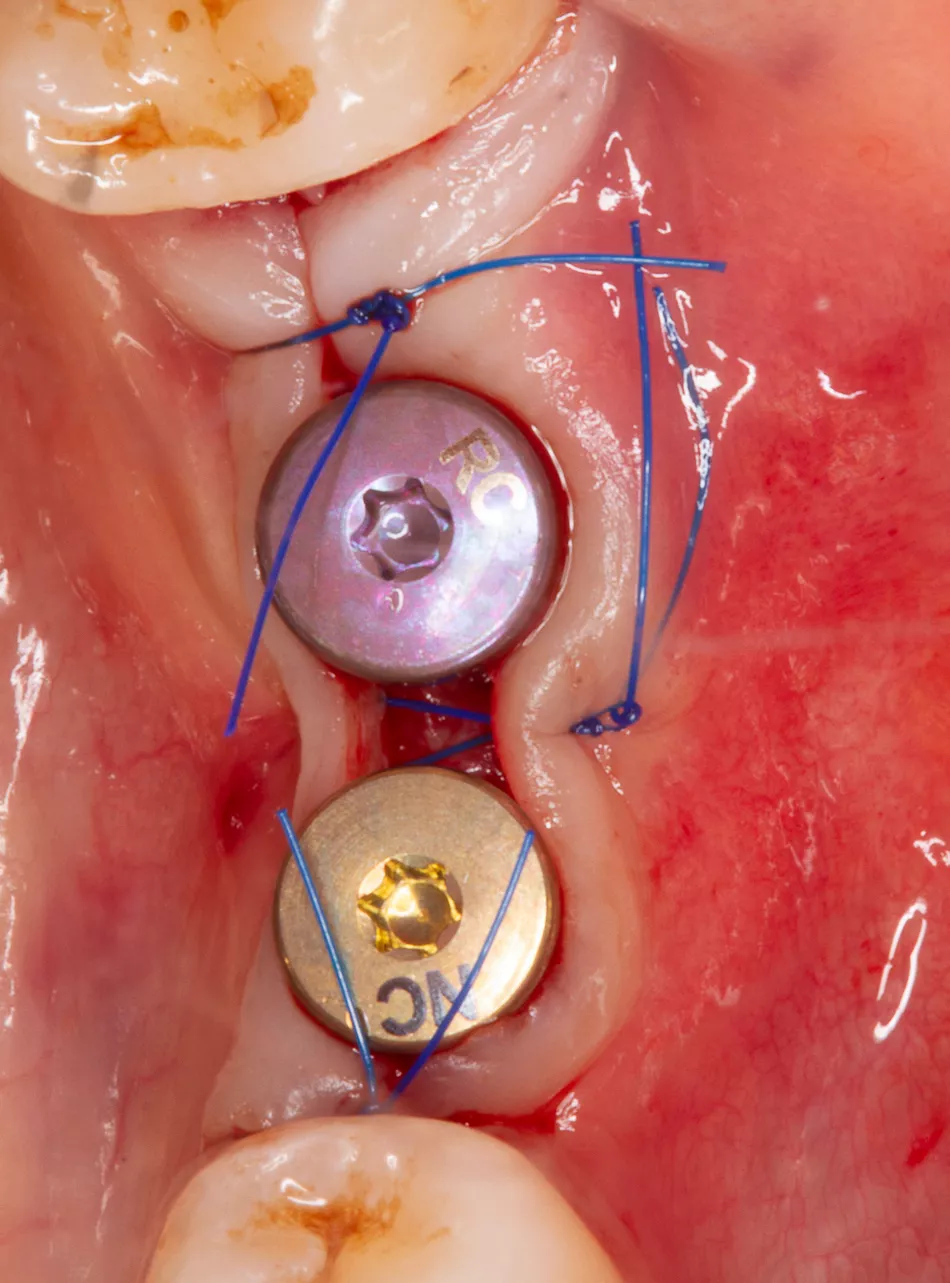

Second-stage surgery involved implant bed preparation and placement of two Straumann® BLT SLA® Roxolid® implants (#36: Ø3.3mm × 10mm; #37: Ø4.1mm × 10mm) with primary stability > 35 Ncm (Figure 9-10).

Healing abutments were placed, and soft tissue closure was achieved with appropriate suturing technique (Figure 11), and implant positions were confirmed with panoramic and periapical radiographs (Figure 12-13).

Figure 11: Healing abutments are placed and soft tissue is sutured